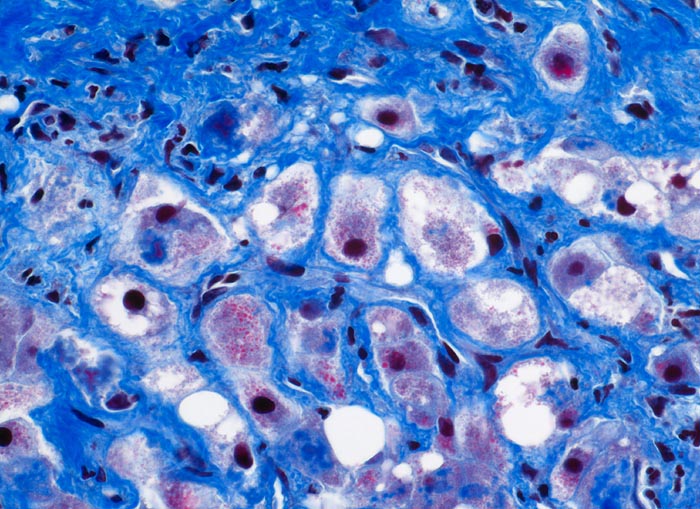

Floride alkoholische Steatohepatitis

Pathologischer Befund